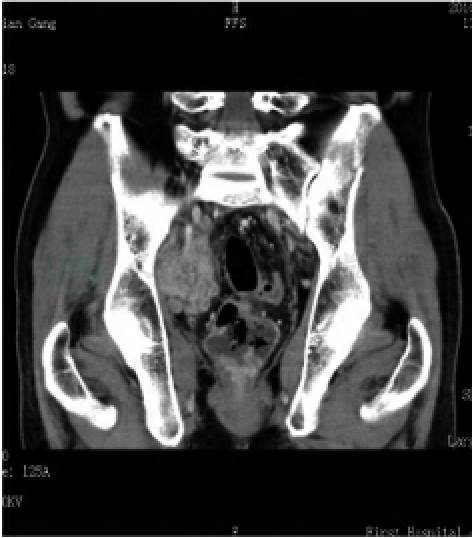

术后4个月,复查盆腔CT,示盆腔团状软组织影,大小约4.9cm×6.0cm×6.0cm,边缘不光整,边界不清,其内密度不均匀,增强扫描明显不均匀强化,考虑膀胱癌盆腔转移灶;盆腔及双侧腹股沟多发淋巴结影,未除外转移可能(图2)。

图2 术后4个月复查CT表现